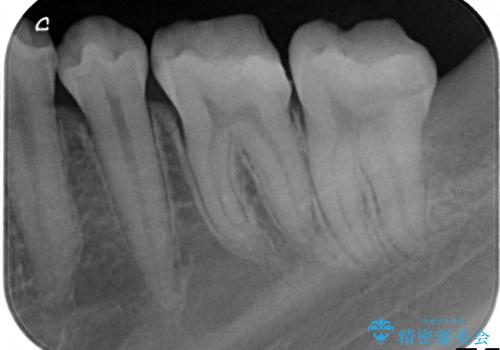

- 左下奥歯がしみるといらっしゃった方の症例です。

左下7の虫歯は深く、また歯冠高径も低かったため、歯冠長延長術を行いました。

術後歯肉の回復を待ち、左下6はセラミックインレー、左下7はオールセラミッククラウンにて補綴しました。